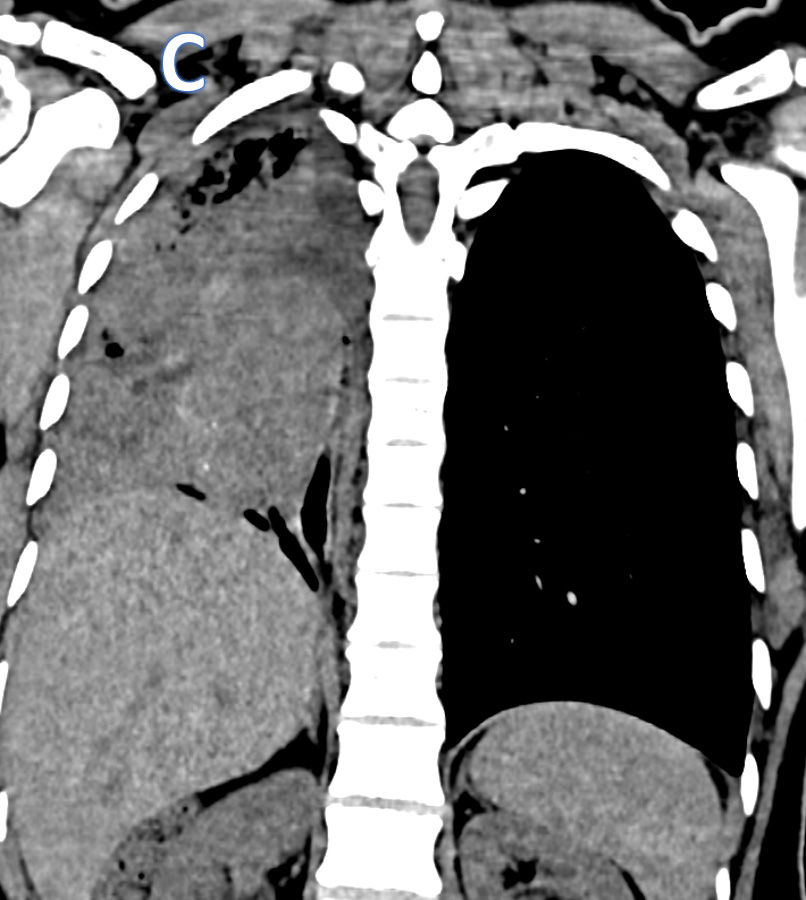

B – Axial CT thorax (soft tissue and lung window images)

• ARROW: Soft tissue density endobronchial mass lesion in the right main bronchus.

• STAR: Collapsed right lung and hypodense  fluid in the right hemithorax.